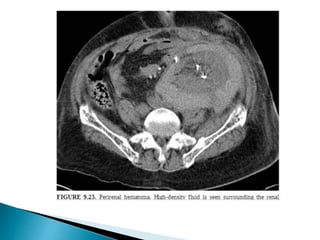

 Imaging

3. Peri-renal hematoma.

1. USG:- hypoechoic fluid collection represents a hematoma within the

laceration/peri-nephric space.

2. CT:- dense clot within the laceration/peri-nephric space.